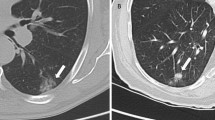

Attenuation of the high-energy photons by patient tissue is a dominant physical effect in PET and SPECT imaging. For PET/CT and SPECT/CT imaging, the attenuation factors can be conveniently derived from the CT image as the same processes affect photon scattering in PET, SPECT and CT [25–27]. For MR imaging, however, the image values typically represent a weighted average of hydrogen proton density and T1 and T2 relaxation times, which are influenced by the local environment [28]. For qualitative PET/MR, current reconstruction algorithms using Dixon-based attenuation corrections yield comparable, and even slightly superior, PET images as evidenced by the improved resolution of the vertebral bodies on the PET images obtained on a Siemens mMR scanner (Fig. 1). However, accurate PET quantification depends on appropriate attenuation correction. MR image values (unlike CT image ones) do not directly reflect the tissue attenuation values, as illustrated by the comparison of the CT with the T2-HASTE MR whole-body images in Fig. 1. Thus, this inaccuracy in the MRI data can confound accurate PET or SPECT quantification. Of particular note is that the MR signal in bone is significantly different from the signal on the CT image. Greater differences in the blood and adipose tissue values are also apparent. Therefore, there is no simple scaling method that can be used to convert the MR image to a CT-equivalent attenuation map. Differences between CT and MR imaging information for lung parenchyma are further illustrated in Fig. 2, which compares CT and T2-weighted MR lung images, illustrating the lower MR intensity values in the lung due to the low density of hydrogen nuclei and possibly also due to susceptibility artifacts from the air–surface interfaces [29].

T2-weighted MRI (a) and (b) CT images of the thorax of the same patient showing the lack of similarity of the physical properties measured [29]. (With kind permission from Springer Science + Business Media)